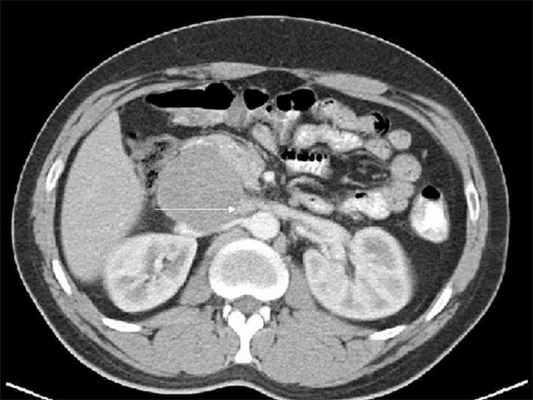

Ультразвуковая эхография помогает определить размеры и глубину расположения опухоли, выяснить ее связь с сосудами; компьютерная томография позволяет определить опухоли диаметром начиная с 1,5-2,0 см, точное их распространение, топографию, обнаружить увеличение лимфатических узлов.